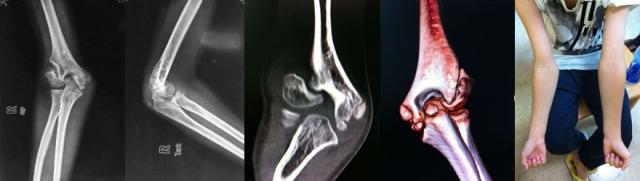

肘关节外翻、过伸

检查方法:上肢完全伸直,测量肘关节外翻、过伸角度。外翻超过20度,过伸超过15度不合格。

肘关节正常约有10度左右外翻,超过10度称之为外翻畸形,肘关节外翻、过伸多是先天导致,极少部分后天外伤导致,一般无自主症状,如果单纯考虑健康问题,大部分肘关节外翻是不需要处置的。

解决办法:肘外翻无法自行矫正,严重时可手术矫正。对于想当兵是否进行手术矫正,其中利弊请自行权衡。